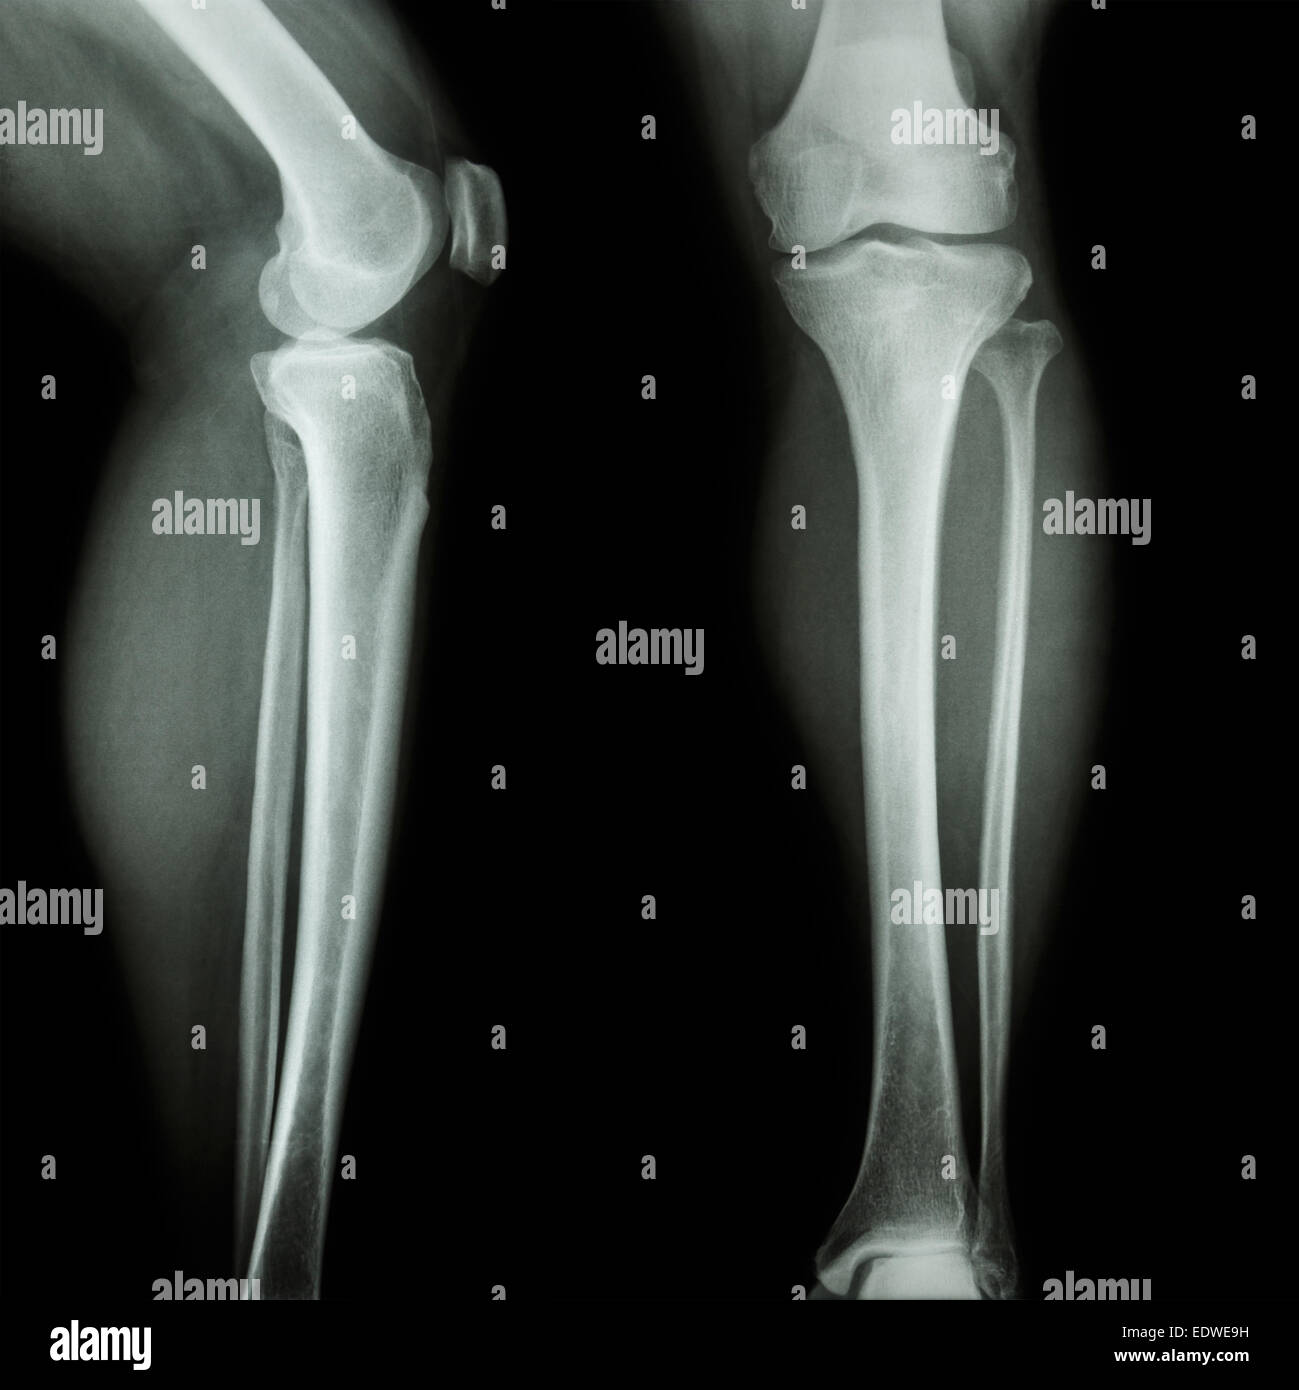

Film X-ray montrent l'articulation du genou normal(AP/latéral) Banque D'Imageshttps://www.alamyimages.fr/image-license-details/?v=1https://www.alamyimages.fr/photo-image-film-x-ray-montrent-l-articulation-du-genou-normal-ap-lateral-77387023.html

Film X-ray montrent l'articulation du genou normal(AP/latéral) Banque D'Imageshttps://www.alamyimages.fr/image-license-details/?v=1https://www.alamyimages.fr/photo-image-film-x-ray-montrent-l-articulation-du-genou-normal-ap-lateral-77387023.htmlRFEDW7X7–Film X-ray montrent l'articulation du genou normal(AP/latéral)